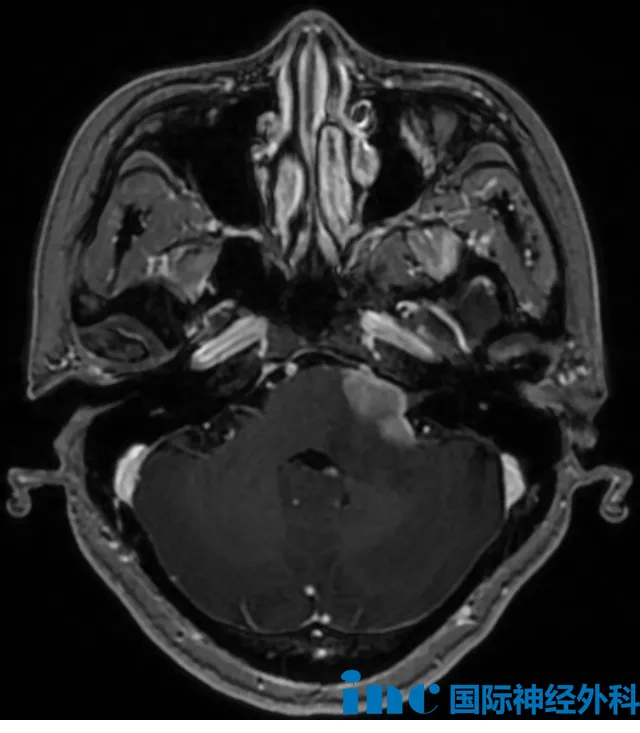

一位61岁的男性患者就遭遇了这种情况——他的舌头已经出现中度萎缩,影像检查显示肿瘤从扩大的舌下神经管一路延伸,向上侵及脑干周围的硬膜内空间,向下则蔓延至高位颈椎区域。...